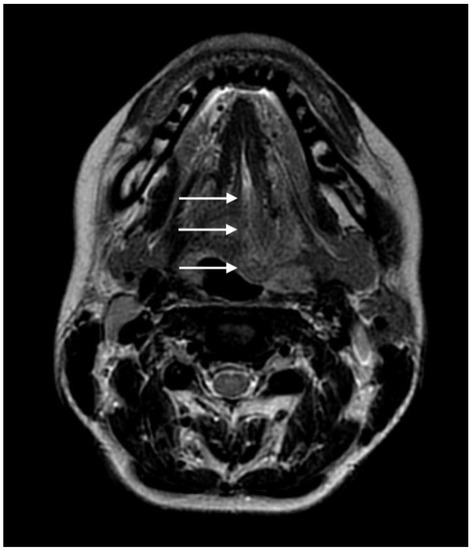

Acute Tongue Swelling as a Still Unexpected Manifestation of Internal Carotid Artery Dissection: A Case Report

The diagnosis of internal carotid artery dissection (ICAD) at the stage of local signs is essential in the prevention of the life-treating cerebral complication; however, making this diagnosis has significant difficulties. We present the case of a 36-year-old female with left ICAD with [...] Read more.

The diagnosis of internal carotid artery dissection (ICAD) at the stage of local signs is essential in the prevention of the life-treating cerebral complication; however, making this diagnosis has significant difficulties. We present the case of a 36-year-old female with left ICAD with asymmetric left-sided tongue swelling as an unusual and still unexpected symptom. The patient’s complaints at admission were left-sided numbness of the tongue and swallowing difficulties but its movements were intact. Despite the provided treatment for suspected angioedema, no improvement was noted. Additional examination revealed left-sided tongue weakness, ipsilateral soft palate palsy, paralysis and reduced tension of the left vocal fold, and left-sided Horner’s syndrome. Another suspected diagnosis was a dysfunction of the IX, X, and XII cranial nerves. A head MRI revealed an intramural hematoma of the left internal carotid artery. The radiologists suggested ICAD. The angio-MRI of the head arteries confirmed this diagnosis. The patient received dual antiplatelet therapy. The neuro-logopaedic therapy was also implemented. Currently, the patient’s symptoms are gradually improving with significantly better results on follow-up neuroimaging. Among the possible local symptoms of ICAD, proper attention should be paid to asymmetric swelling of the tongue as an atypical manifestation of damage to the hypoglossal nerve. Full article

Show Figures

Figure 1